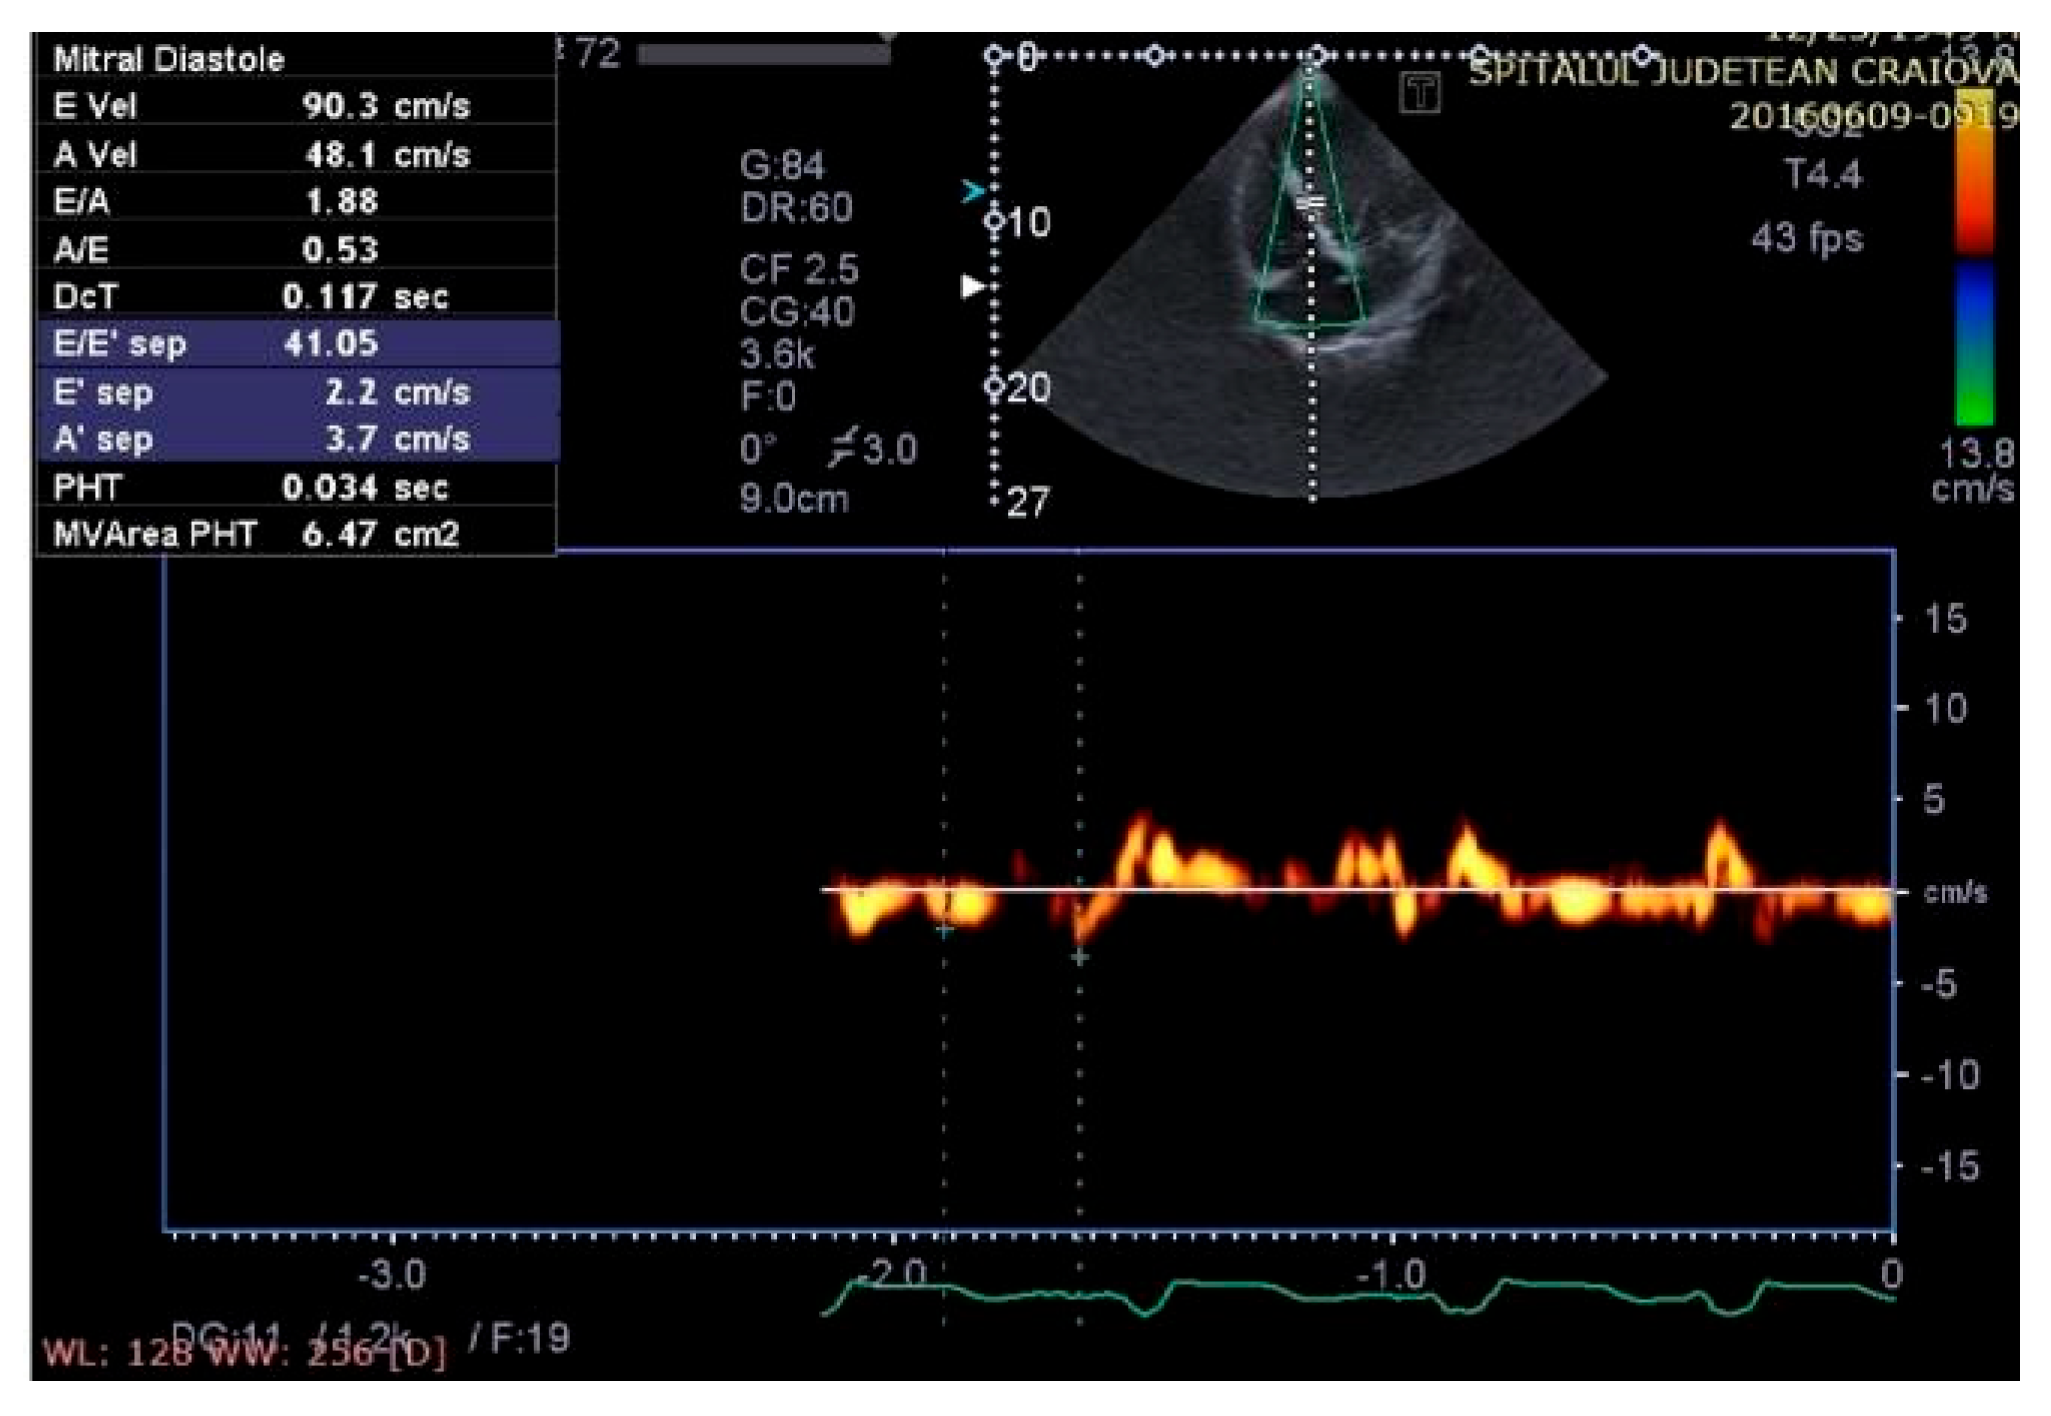

Some echocardiographic aspects revealed in the transthoracic echocardiographic examination before and after CRT are presented in Figure 3, Figure 4, Figure 5, Figure 6, Figure 7, Figure 8 and Figure 9.

Figure 3.

Assessment of myocardial strain from the apical four-chamber view, before therapy with a cardiac resynchronization device.

Aspect of waveforms of tissue Doppler interrogation at the interventricular septum before therapy with a cardiac resynchronization device (yellow color).